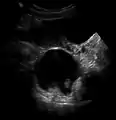

A small (4 cm) dermoid cyst of an ovary, discovered during a C-section

Ovaries normally grow cyst-like structures called follicles each month. Once an egg is released from its follicle during ovulation, follicles typically deflate. Sometimes fluid accumulates inside the follicle, forming a simple (containing only fluid) cyst.[2] The majority of these functional cysts resolve spontaneously.

While all ovarian cysts can range in size from very small to quite large, dermoid cysts are not classified as functional cysts. Dermoid cysts originate from pluripotent germ cells (which are present at birth) that differentiate abnormally, developing characteristics of mature dermal cells. Complications exist, such as torsion (twisting), rupture, and infection, although their incidence is rare. Dermoid ovarian cysts which are larger present complications which might require removal by either laparoscopy or laparotomy (traditional surgery).[3][4] Rarely, a dermoid cyst can develop in the vagina.[5][6][7]